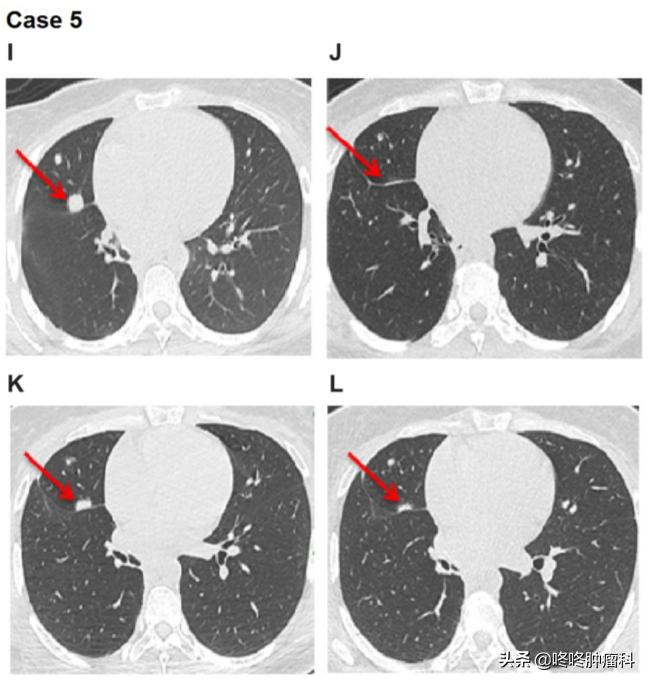

I:2018年1月治疗前的评估;J:2018年5月,阿法替尼治疗达PR的评估;K:2018年6月,疾病进展的评估;L:2018年8月提高剂量到50毫克/天达PR的评估

检测结果显示患者有 SDC4-NRG1融合 。患者直接使用阿法替尼40毫克/天作为1线治疗,使用6周后,评估为PR。

5个月后肺部出现进展,但治疗并未就此结束,医生选择给患者增加阿法替尼剂量为50毫克/天,惊喜地再次观察到PR,持续6个月。随后患者接受了其他疗法。